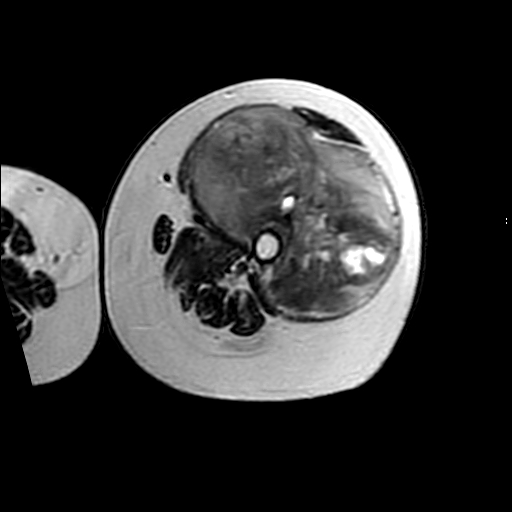

左侧大腿外伤10余年,当时情况不清,发现左侧大腿肿胀7年余,而后又有多次外伤史,近1年来出现疼痛,减重半年。查体:左侧大腿肿胀明显,皮温、肤色正常。

软组织肿块,股骨破坏,增强不均匀强化-----支持恶性肿瘤